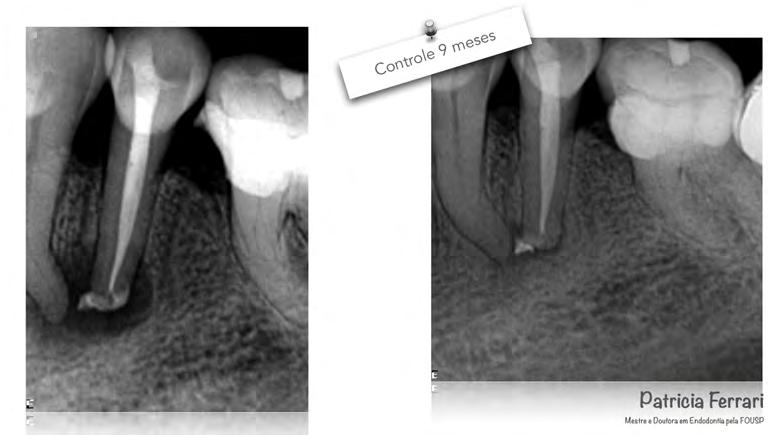

Prof. Dra. Patricia Ferrari

07/2018

Femenino

44 años

Periodontitis Apical asintomática. Desobturación, Preparación Químico-Mecánica, Sistemas de limpieza definitiva, Terapia Fotodinámica antimicrobiana (aPDT) y Medicación Intraconducto. 10/2018

P. O. 9 meses

Cirujano Dentista

Inicio del tratamiento

Género del paciente

Edad del paciente

Diagnóstico inicial

Protocolo utilizado

Fecha del seguimiento

O. 4 meses

06/2018

62 años

Absceso Periapical Agudo.

Preparación Químico-Mecánica, Sistemas de limpieza definitiva, Terapia Fotodinámica antimicrobiana (aPDT) y Medicación Intraconducto. 11/2018